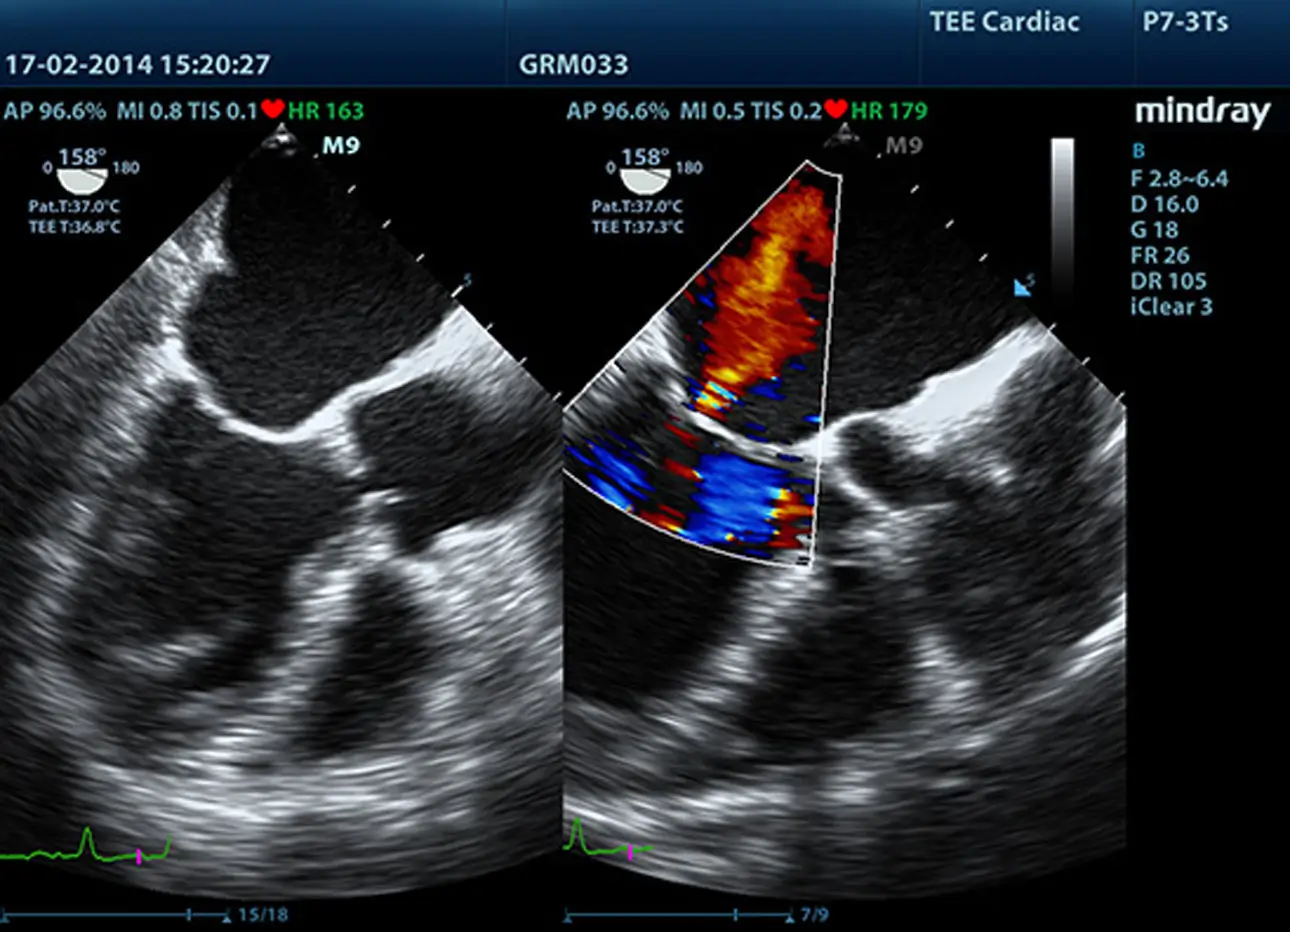

Zaawansowane elementy do przesyłania i odbierania sygnału zapewniają wysoką czułość i dokładność wykrywania echa. Innowacyjne technologie zastosowane w sondach pozwalają na lepszą penetrację i wyższą rozdzielczość, co znacznie poprawia możliwości diagnostyczne.

Sondy wykonane w technologii 3T

Opatentowana technologia wykorzystywana w sondach Firmy Mindray zwiększa zakres obrazowania i wydajność transmisji.

- Dzięki potrójnej warstwie dopasowania uzyskujemy lepszą czułość, szerszy zakres obrazowania i lepszy współczynnik sygnał / szum (S/N)

- Konstrukcja z całkowitym odcięciem wpływa na zmniejszenie zakłóceń, lepszą kierunkowość i poprawę rozdzielczości

- Kontrola termiczna polepsza transmisję akustyczną.